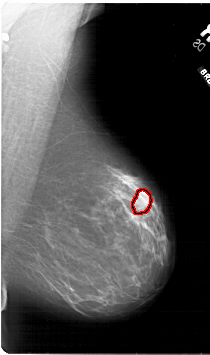

A_1813_1.RIGHT_CC

RIGHT_CC LINES 6481 PIXELS_PER_LINE 4186 BITS_PER_PIXEL 12 RESOLUTION 43.5 OVERLAY

FILE: A_1813_1.RIGHT_CC.OVERLAY

TOTAL_ABNORMALITIES 1

ABNORMALITY 1

LESION_TYPE MASS SHAPE LOBULATED MARGINS ILL_DEFINED

ASSESSMENT 4

SUBTLETY 3

PATHOLOGY BENIGN

TOTAL_OUTLINES 1

BOUNDARY